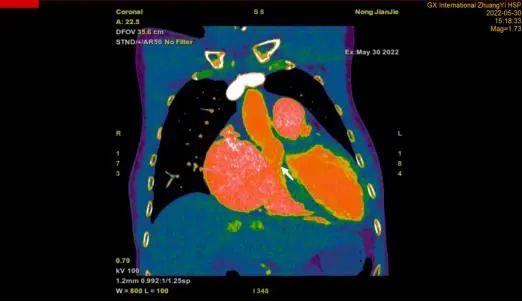

CTA检查:箭头所指为主动脉窦瘤破裂至右心的异常通道

徐先增介绍,主动脉窦瘤为先天形成,因其诞生于主动脉窦部而得名。随着患者年龄增长,主动脉窦瘤会在慢慢增大的同时,进入患者心脏,增大到一定程度后会因瘤壁变薄而破裂,破入心脏的右心房、右心室、肺动脉等处,若破入心包可迅速引发死亡。农先生的主动脉窦瘤破裂,为从右主动脉破入右心房的状况,破裂后使右主动脉和右心房之间形成了异常通道,导致其左心房的血液不断流向右心房,极大地增加了右心室的负荷与体积,最后导致心衰。